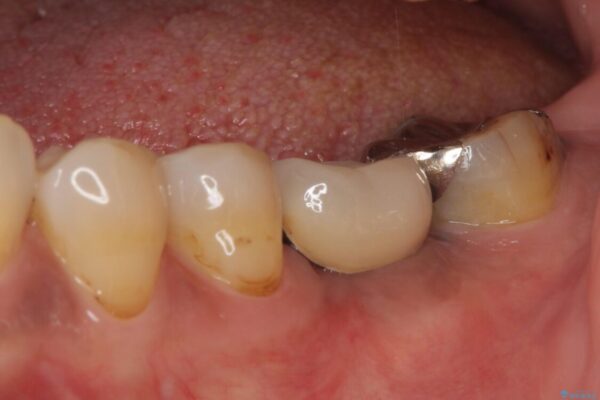

治療前

• しみる奥歯 オールセラミッククラウンによる補綴治療 治療前画像

銀歯の装着されている奥歯がしみるとのことで来院された患者様です。

銀歯周辺の歯が欠けており、むし歯も進行している状態であったので、オールセラミッククラウンにて補綴治療を行うこととしました。